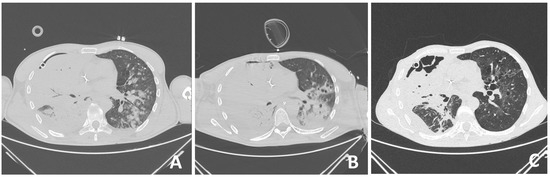

On this outpatient examination, a CT scan of the lung was performed, which confirmed bullous changes in the left side of the lung (Figure 4). Subjectively, he had discomfort when breathing and pain in the right chest. He complained about poor physical condition. His medical therapy prescribed by a pulmonologist was ipratropium bromide (Atrovent N, Boehringer Ingelheim Pharma GmbH & Co., Ingelheim, Germany) 3 × 2 breaths.

High ventilation pressures can improve oxygenation but may increase the risk of barotrauma in the healthy lung. Due to lower resistance, a larger volume of inhaled gas will be directed to healthy areas of the lungs [17]. This is the reason why the strongest bullous changes after mechanical ventilation in our patient were found on the follow-up CT after discharge in the lung areas that were less affected by trauma and inflammation, i.e., in the upper left lung lobe.

Figure 4. The horizontal CT scan section at the level of the 6th thoracic vertebra (A) and at the level of the 3rd thoracic vertebra (B) showing residual bullous changes (arrows) 6 months after severe chest injury with bilateral pneumonia in a 53-year-old patient.